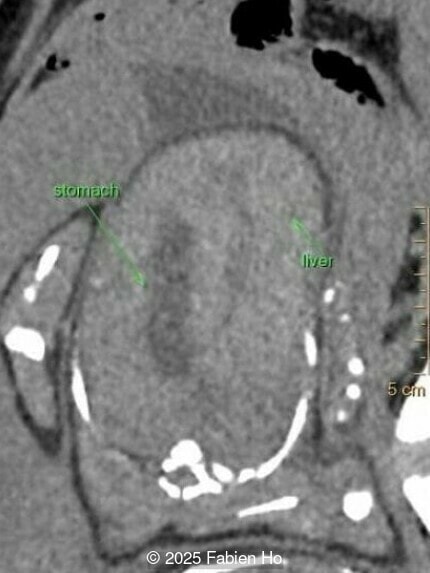

Our prenatal ultrasound revealed a male fetus with megabladder, dilation of both ureter and kidneys, and thinned kidney parenchyma consistent with Lower Urinary Tract Obstruction (LUTO). Additional findings suspected on ultrasound and confirmed on computed tomography included:

- Suspicion of dilated bowel in the left flank, in addition to dilated urinary tract